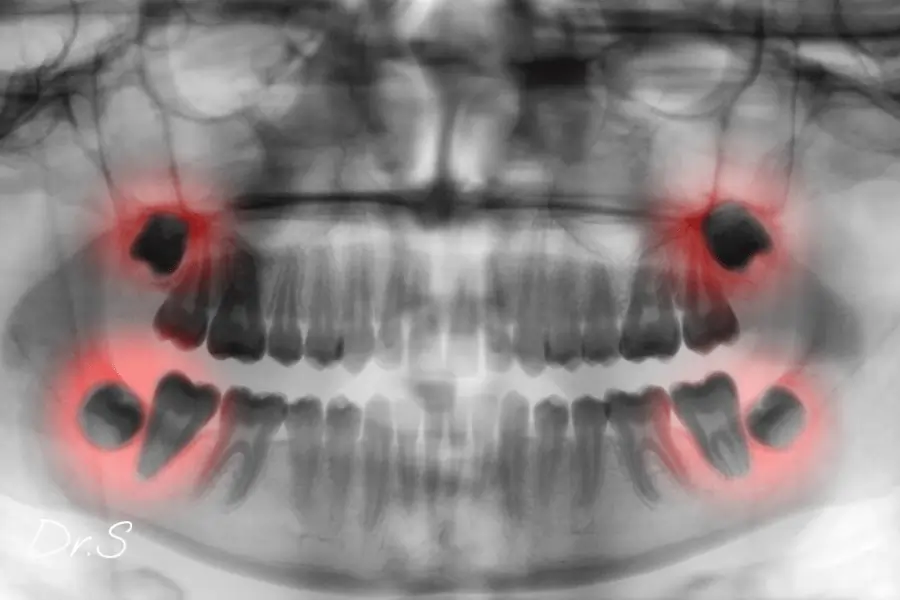

Pourquoi parle-t-on d’imagerie 3D avant une extraction sous anesthésie locale dent de sagesse ?

Quand la radio ne suffit pas, la 3D aide à situer racines et nerf. C’est un outil d’aide au diagnostic, à utiliser avec prudence, selon votre situation.